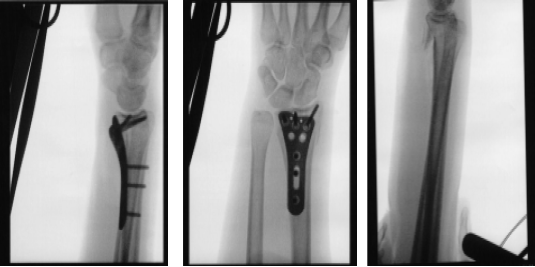

Following a fall, the patient, a 27-year-old female, complains of pain in her right wrist. She has her arm in a brief splint. She underwent a CT scan and x-ray. The distal end of the right side of the radius was found to have a comminuted intra-articular (more than three fragments) fracture after reviewing and discussing the CT and X-ray images.

X-ray wrist 3 or more view

Once the reduction was achieved, Fluoroscopy showed fracture in acceptable position. The plate was put onto the distal radius and held with olive wires. Finding it in acceptable position on fluoroscopy, the plate was fixed distally by the use of a cortical screw, which was later changed to a locking screw.

Once the plate was in good position, fixation of the proximal fragment with the plate was done by the use of three cortical screws. This was followed by fixation of the distal fragment with the use of locking screws. The central screw was removed and wasted and a locking screw was inserted. The fixation was found to be satisfactory. Final pictures were taken and saved.

After one week the patient visits the office for her post operative consultation with x-rays of her twist. Her pain is well controlled, she denies fever and chills.